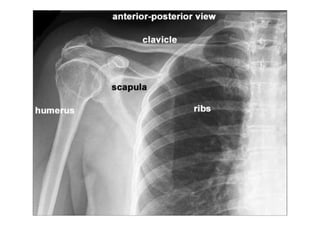

RADIOLOGIA DO

TRAUMA DO ESQUELETO

Referência: http://www.accessexcellence.org/RC/VL/